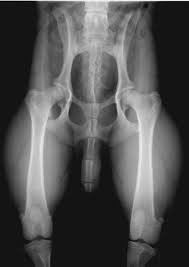

Dat ziet er helaas niet goed uit. De heupkommen zijn ondiep en de koppen liggen niet goed aangesloten in de kommen.

Ja, ik ben bang dat dit inderdaad HD is. Een slechte aansluiting, onvoldoende overlap tussen de kop en de kom; 'hip laxity' (losse heupen).

Onze hond heeft ook HD en op de foto's die gemaakt zijn toen ze 18 maanden oud was zaten de heupen iets beter in de kommen dan op jouw foto, en onze hond heeft de diagnose HD-C gekregen.